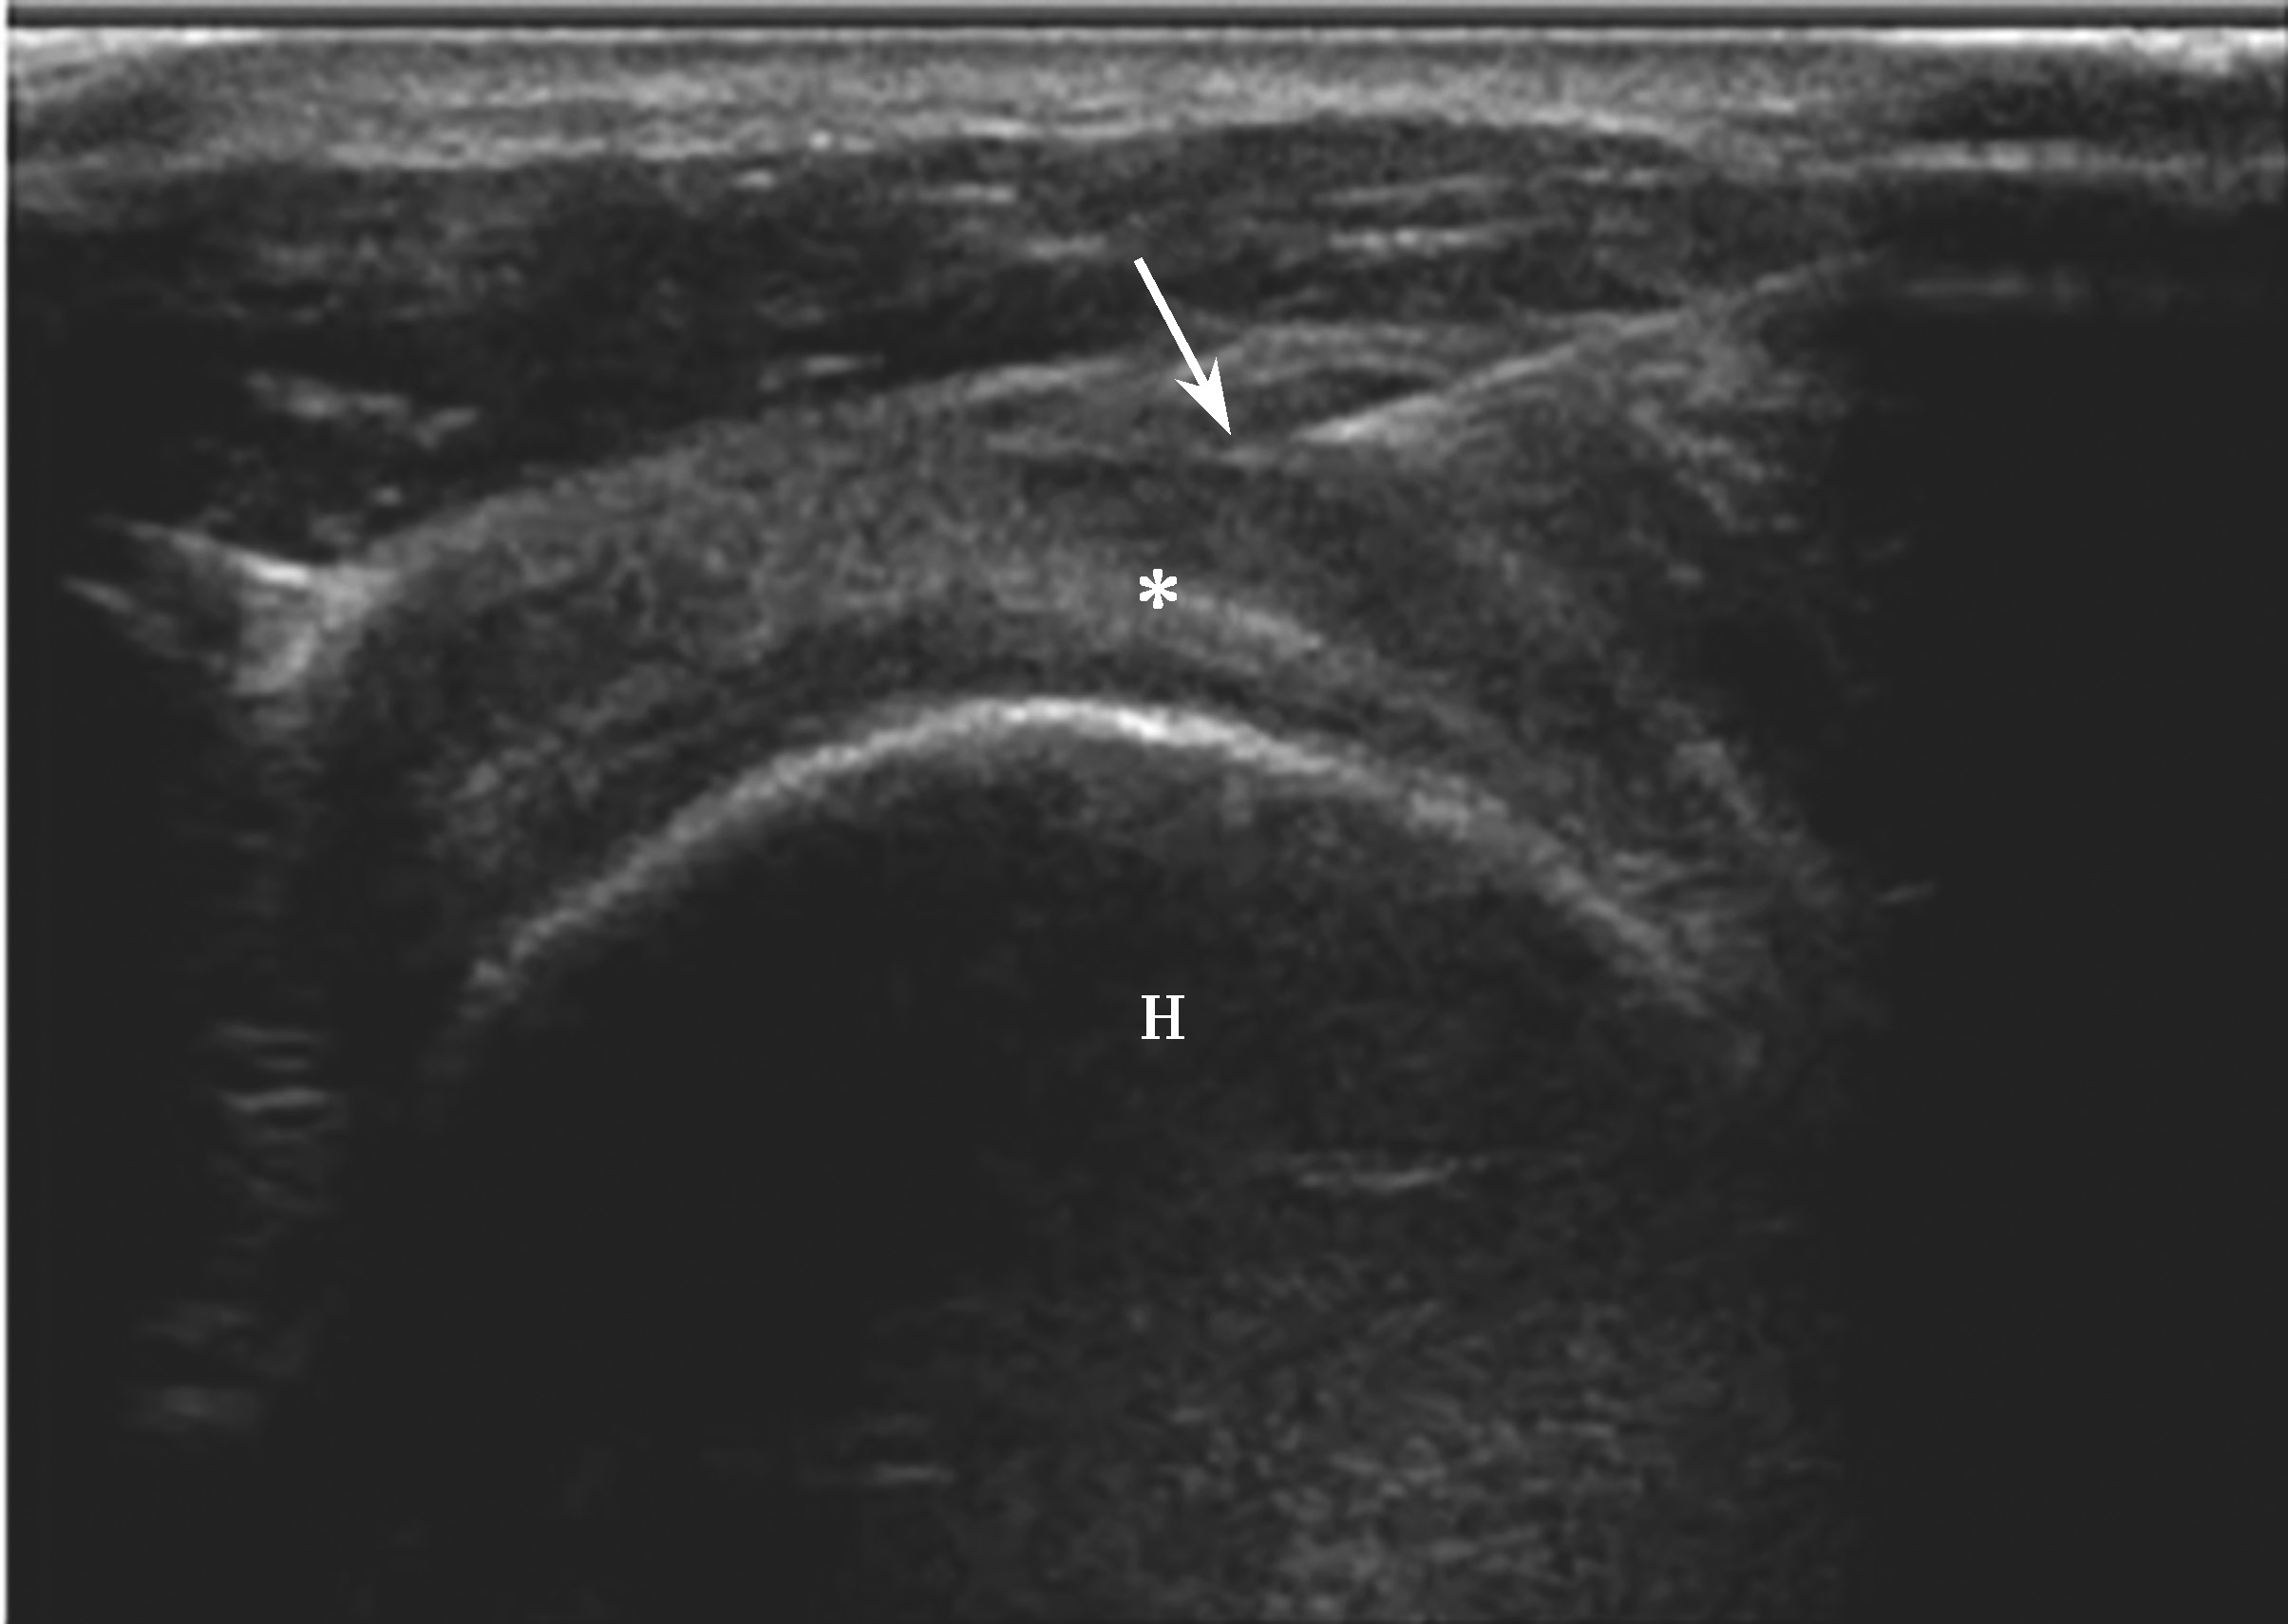

2.当针尖进入滑囊后(图2-1-5),可推注少量药物,若推注顺利可观察到滑囊扩张及药物的弥散(图2-1-6),同时也表明针尖准确位于滑囊内,可继续推注混合药物3~5ml。若推注受阻,原因有可能是针尖在滑囊组织内,需重新调整针尖,也可能是滑囊内粘连明显所致,可加大力度,利用液体推注的压力松解粘连,松解后可见粘连带呈线状稍强回声(图2-1-7),也可在粘连远端重新选择部位注入药物,这类患者可能需要多次治疗才能达到较好的疗效。

▲ 图2-1-5 超声引导下肩峰下-三角肌下滑囊穿刺治疗超声图

箭头:显示穿刺针尖进入滑囊;星号:冈上肌腱;H:肱骨头